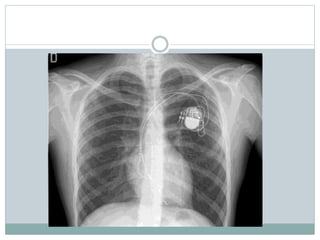

AICD

 The automatic implantable cardioverter-defibrillator

(AICD) is a device designed to monitor the heartbeat.

This device can deliver an electrical impulse or shock

to the heart when it senses a life threatening change

in the heart’s rhythm like sustained ventricular

tachycardia or fibrillation

Bikash is 13 yrs male student diagnosed with

brugada syndrome type 2, managed with AICD dual

chamber is discharged in stable condition with

uneventful hospitalization period.